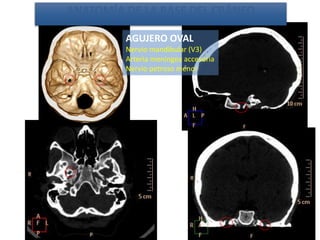

AGUJERO OVAL

Nervio mandibular (V3)

Arteria meníngea accesoria

Nervio petroso menor